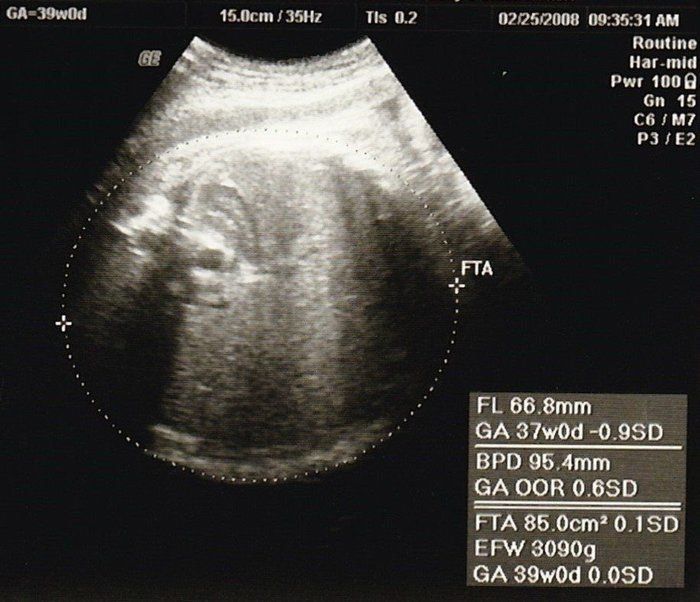

ママにエールさんの妊娠39週目のエコー写真

子宮口は前より柔らかくなってきているけれど、3cm位しか開いていないとのこと。「そろそろ産みたいでしょ」と、先生が言って、子宮を柔らかくする薬を入れました。「赤ちゃんの良いタイミングで、無事に生まれてくれますように」そう祈る気持ちでいっぱいでした。